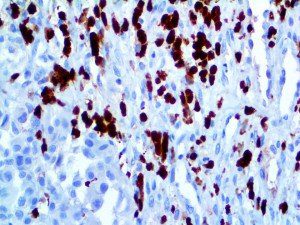

It is the ICU physician who is most likely to witness one of the deadliest manifestations of the abnormal immunological response, the cytokine storm syndrome (CSS). This response is also referred to by some as the cytokine release syndrome (CRS). CSS is characterized by continuous activation and expansion of macrophage and lymphocyte populations, which secrete large amounts of cytokines, causing the cytokine storm. This massive cytokine release is akin to hemophagocytic lymphohistiocytosis (HLH) disease, a syndrome characterized by initial unchecked and persistent activation of cytotoxic T lymphocytes and NK cells.

Clinical and laboratory manifestations of HLH include fever, enlarged liver and/or spleen, neurologic dysfunction, coagulopathy, liver dysfunction, cytopenias (i.e., low levels of erythrocytes, leukocytes, and/or platelets), hypertriglyceridemia, hyperferritinemia, hemophagocytosis, and eventually diminished NK cell activity as the immune system becomes progressively paralyzed. HLH can be familial (primary HLH) or secondary to another disease process (sHLH), such as rheumatic disease, in which it is referred to as macrophage activation syndrome (MAS, characterized by elevated ferritin).